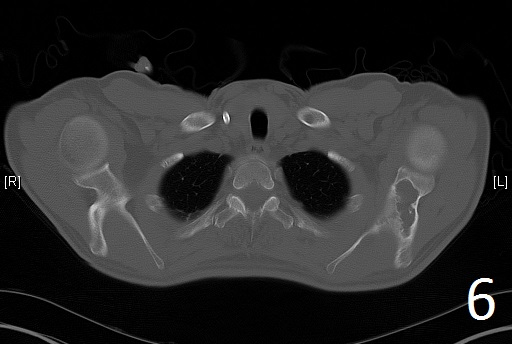

Fig. 6

Fig. 6-7. Axial CT reconstruction of the chest showing lytic and expansile lesion of the left scapula and ribs (polyostotic fibrous dysplasia).